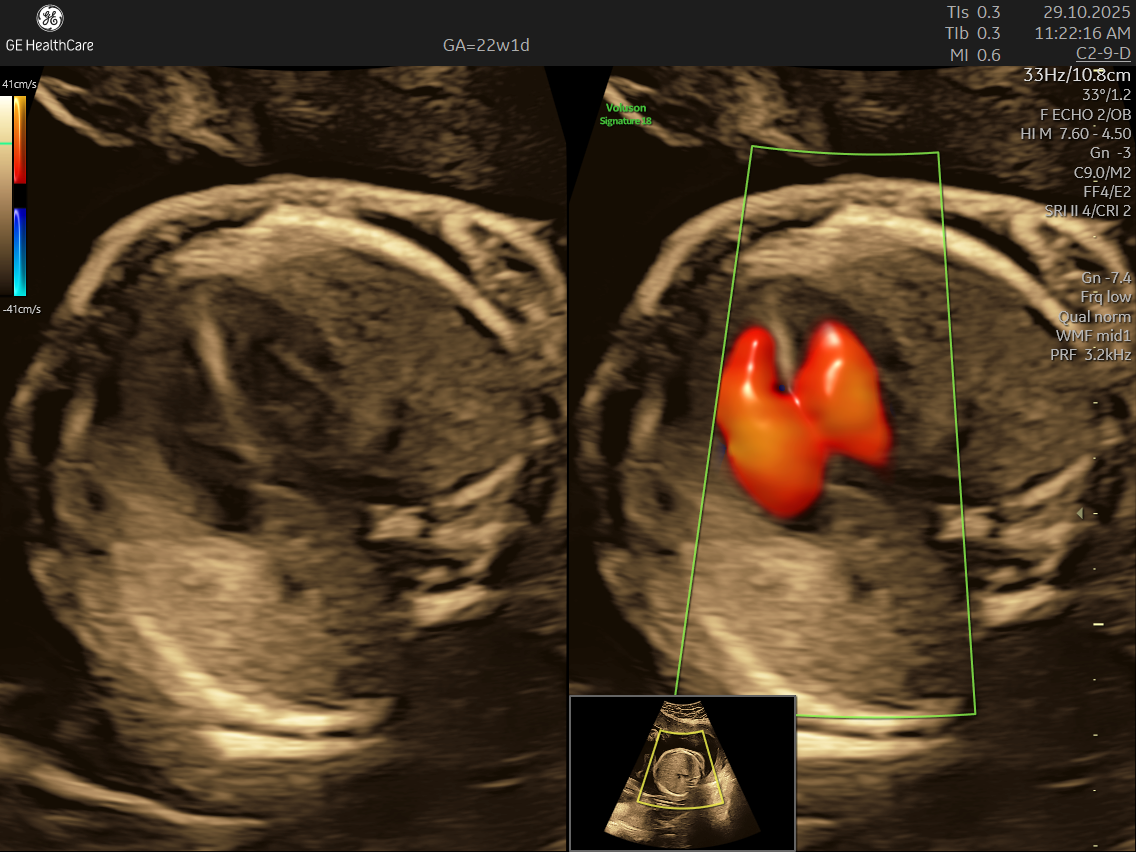

- High Detail: Utilizing advanced Doppler ultrasound technology, it tracks blood movement through the heart and valves, highlighting issues that general scans often cannot detect.

- Blood Flow Patterns: Detects arrhythmias or irregular heartbeats and checks for efficient circulation through the heart and major vessels.

- Abnormalities in blood flow patterns and valve function observed on Doppler imaging.

- Using the advanced GE Voluson S10 ultrasound machine—renowned for its superior imaging clarity, 4D real-time visualization, and automated analysis tools that significantly increase diagnostic accuracy and reduce the chances of missing subtle heart defects.

- Its a specialized ultrasound done between 18–24 weeks of Gestational Age that evaluates the structure, function, and rhythm of a baby’s heart while still in the womb. This scan uses high-frequency sound waves to create detailed images of the fetal heart, aiding in the detection of congenital heart defects (CHDs) and other abnormalities.